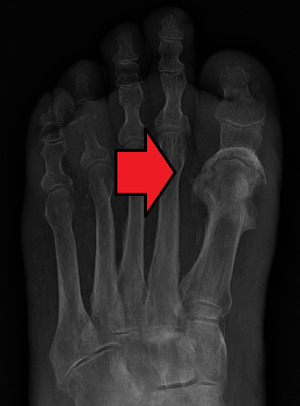

Osteomyelitis of the 1st toe

Extensive osteomyelitis of the forefoot

Radiographs and CT are the initial method of diagnosis, but are not sensitive and only moderately specific for the diagnosis. They can show the cortical destruction of advanced osteomyelitis, but can miss nascent or indolent diagnoses.[21]

Diagnosis of osteomyelitis is often based on radiologic results showing a lytic center with a ring of sclerosis.[12] Culture of material taken from a bone biopsy is needed to identify the specific pathogen;[24] alternative sampling methods such as needle puncture or surface swabs are easier to perform, but do not produce reliable results.[25][26]